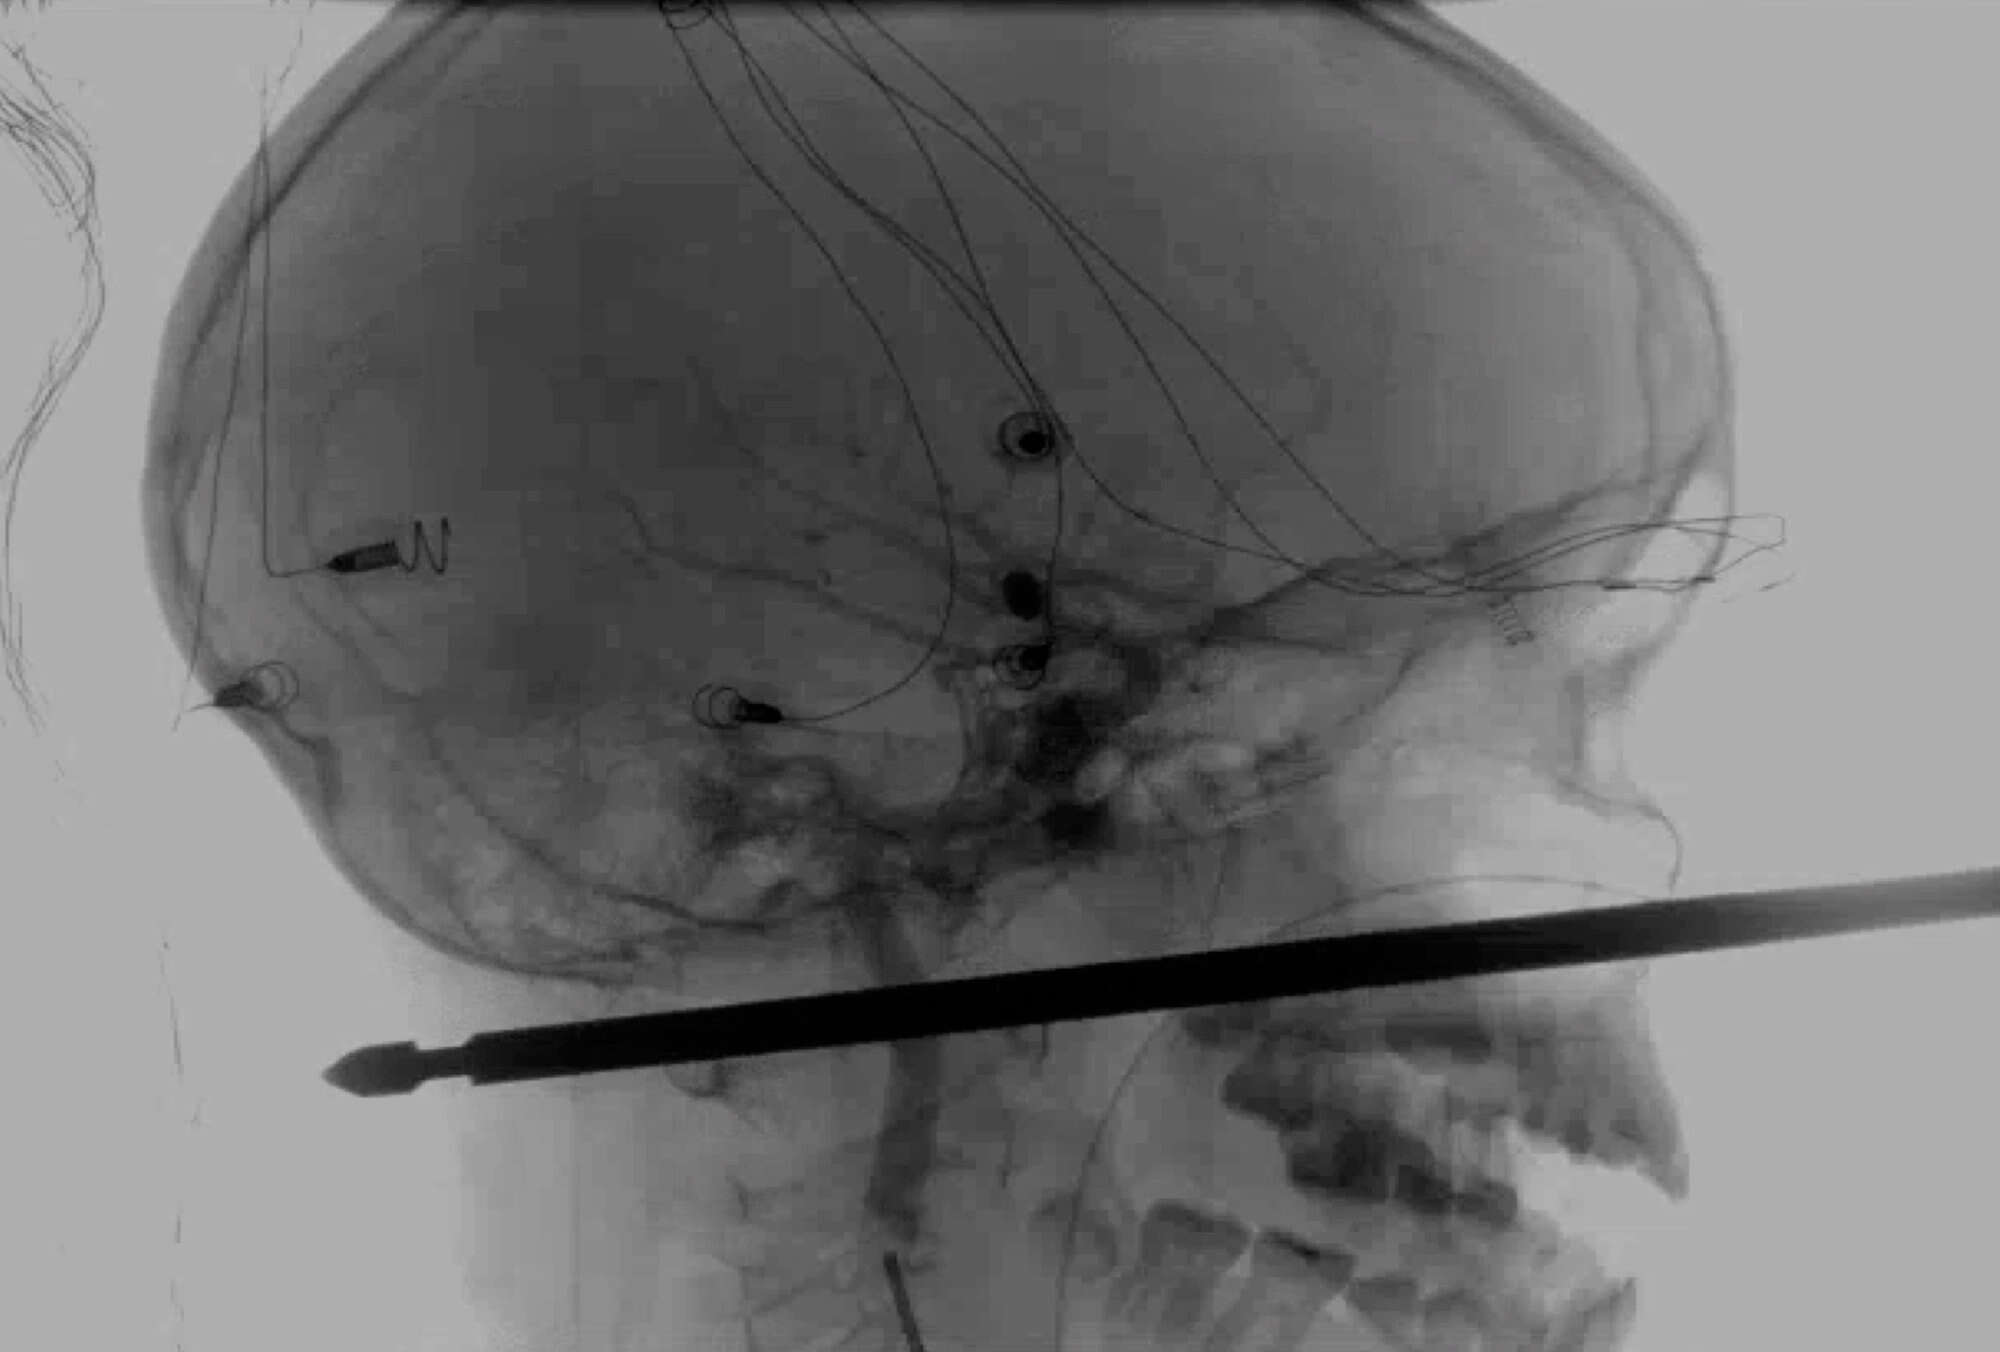

נס בארה"ב: בן 10 ממיזורי הצליח לשרוד, למרות ששיפוד בשר חדר לראשו. המקרה המדהים התרחש לאחר ששאבייר קאניגהאם נפל בשבת האחרונה מבית עץ, בעת שניסה לברוח מלהקת צרעות שתקפה אותו, ונפל עם פניו על השיפוד.

באורח פלא השיפוד פספס את עיניו, מוחו, חוט השדרה וכלי הדם. מבית החולים האוניברסיטאי בקנזס נמסר כי קאניגהאם צפוי להתאוששות מלאה, אולם קולו עלול להיפגע.

קבוצת רופאים בבית החולים הצליחה להוציא את החפץ במהלכו של ניתוח מסובך שארך כמה שעות. שאבייר שיחק בביתו בהאריסונוויל, כשלהקת הצרעות הצהובות תקפה אותו.

הוא נפל עם פניו על שיפוד באורך של 30 ס"מ, שחדר לעומק של 15 ס"מ לתוך הגולגולת שלו. אמו של הילד, גבריאל מילר, טענה בפני התקשורת המקומית כי ראתה את הילד שלה רצץ אל תוך הבית, כשהוא צורח, בזמן שהשיפוד מבצבץ מראשו.

שאבייר הובהל לבית חולים מקומי, לאחר מכן הועבר לבית חולים בקנזס והועבר שוב בהמשך לבית חולים האוניברסיטאי בעיר, שם כאמור עבר את הניתוח. ד"ר קוג'י אברסולה, אחד הרופאים שניתח את הילד הגדיר את ההתאוששות שלו כ"פלאית" והוסיף כי לא ראה "מישהו שהתאושש מחדירה של חפץ בעומק כזה, ובטח שלא באורח מלא".